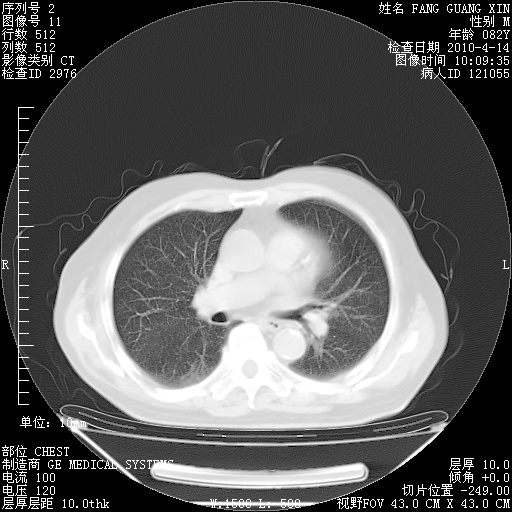

4月14日肺部CT

23.JPG

24.JPG

25.JPG

26.JPG

肺部CT平扫未见异常。

4月28日肺部CT——再次出现类似去年5月9日——透光度降低,(影像科认为)“间质性”改变。

4月28日肺部CT——再次出现类似去年5月9日——透光度降低,“间质性”改变。